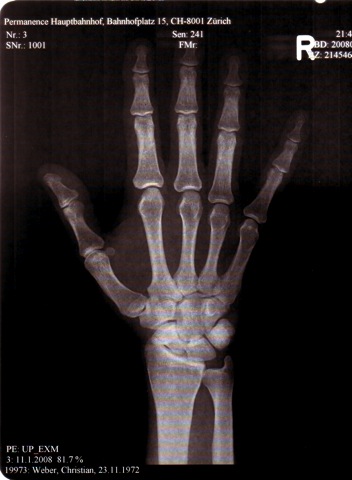

- Gaining new insights via bike crash

January 11th 2008

© unknown nurse